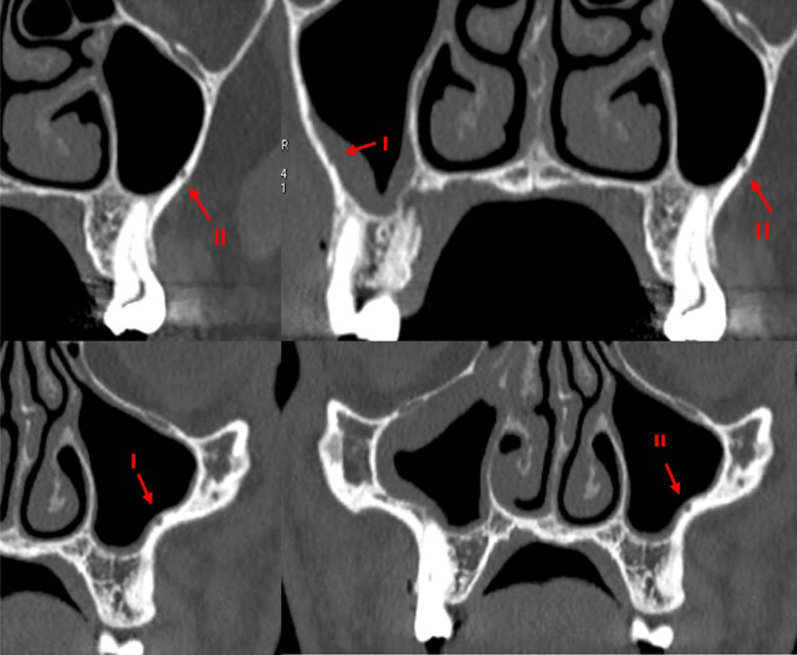

Fig. 6.

Different orientations of MSS: (A) sagittal, (B) sagittal + bucopalatal, C, D transversal